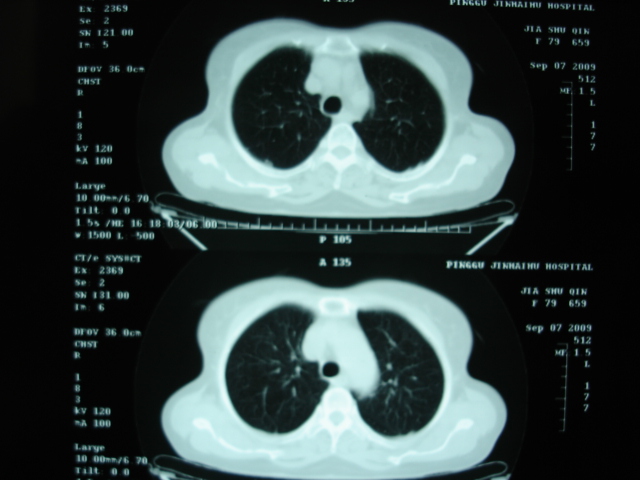

以下是引用卜一在2009-9-7 19:51:00的发言:[br][br] 1 左侧胸内甲状腺占位-多考虑甲状腺腺瘤! 2、左肺门占位-建议增强扫描以便明确性质。 3 慢支并感染! [br]

以下是引用shibing在2009-9-7 20:40:00的发言:[br]左侧胸内甲状腺占位-多考虑甲状腺腺瘤! 2、左肺门占位-建议增强扫描以便明确性质。 3 慢支并感染! [br]